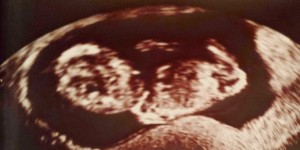

Erste Bilder von dir

So haben wir dich zum ersten Mal gesehen.